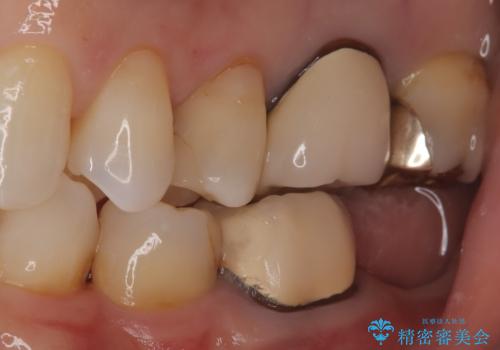

- 奥歯の被せ物が欠けたを主訴に来院された患者様です。欠けてしまった被せ物を除去後セラミックインレーで治療を行いました。

欠けた範囲が大きく被せ物を外して後、セラミックインレーで治療を行いました。欠けたままの状態を放置しているとそこに食べ物が詰まり虫歯になってしまうので早めの治療が必要です。